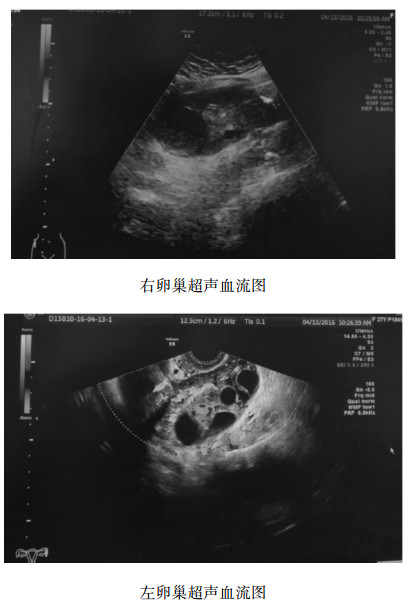

1.2 临床表现移植后24 d,无明显诱因下出现下腹痛,以右下腹为甚。就诊当地医院,超声提示卵巢扭转可能,急诊转至我院,我院急诊超声示:子宫略微大,宫腔内见两个胚囊,未见胚芽,双卵巢增大,均见多房囊性。右卵巢大小11.6 cm×10.3 cm×5.6 cm, 位置偏高位于右侧脐旁,右卵巢内未见明显血流信号。左卵巢大小8.8 cm×6.5 cm×5.2 cm, 左卵巢内血流无殊,左右卵巢超声血流如图 1。

|

| 图 1 患者卵巢超声血流图 |

|

|

超声诊断为宫内早孕,右卵巢扭转可能。急诊予拟卵巢扭转收住入院,入院体检:体温37 ℃,脉搏106次/min,呼吸18次/min,血压123/73 mmHg (1 mmHg=0.133 kPa); 妇科双合诊:子宫前位,无阳性体征,双附件区增厚,右附件区压痛明显,左附件区无压痛,阴道直肠膈无特殊。血HCG 18 686 U/L, 血常规、血凝、生化未见明显异常。结合患者病史,体格检查及超声等检查结果,入院诊断:右卵巢扭转,宫内早孕。